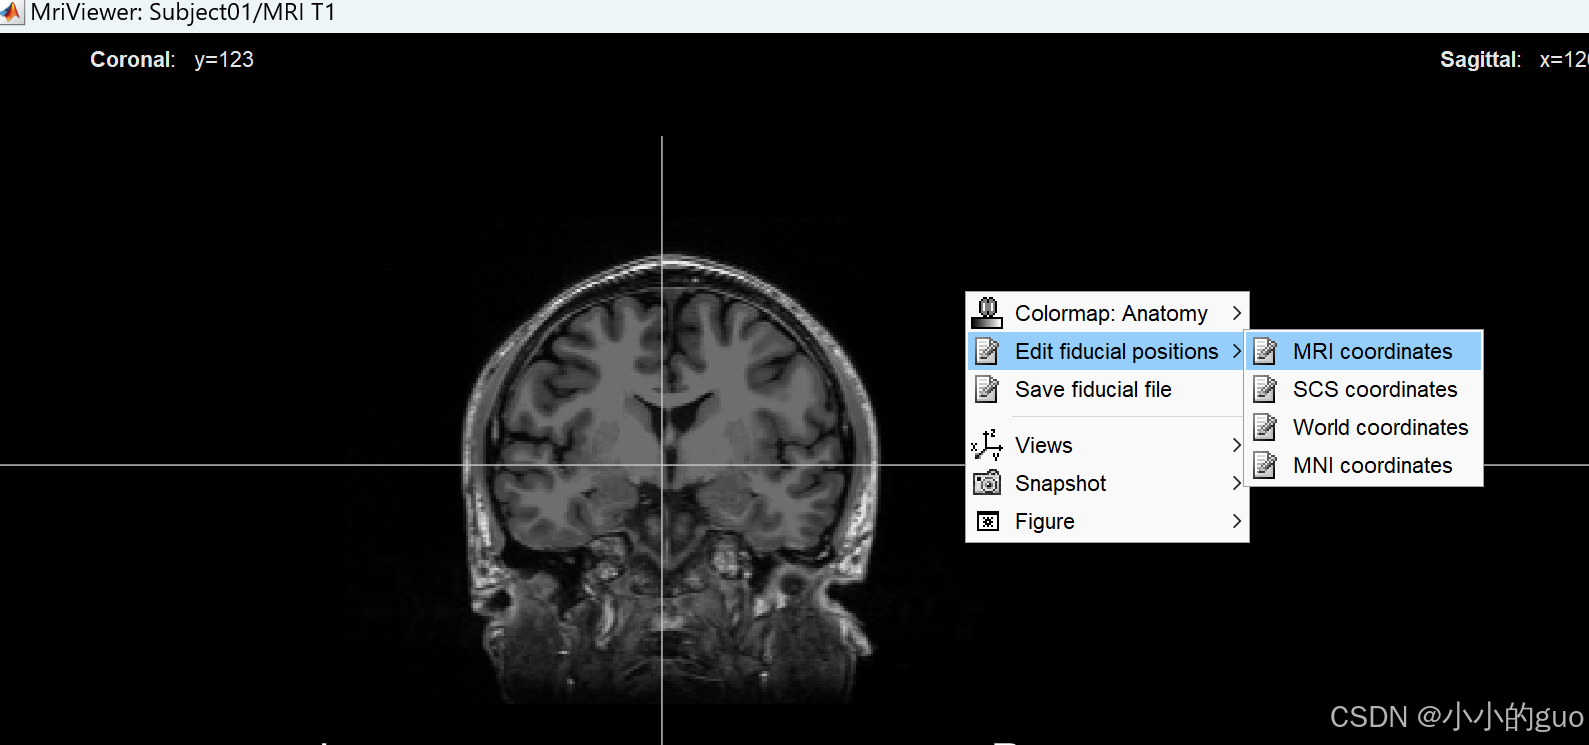

弹出MRI界面,在图像上右键 -> Edit fiducial positions -> MRI coordinates,弹框中输入数值,数值是根据链接1中给出的输入: